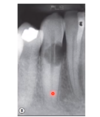

this image shows the Heithersay 1999 clinical classification of cervical resorption. What do each class indicate.

Class 1 - small with shadow penetration Class 2 – close to coronal pulp, no radicular extensions Class 3 – deeper but not beyond coronal third Class 4- extensive beyond coronal third